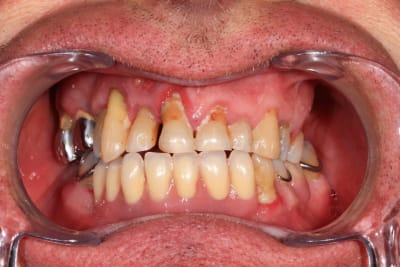

:) . effectivement terrain paro chronique, déjà traité il y a quelques année a paris. Plus ou moins stabilisé, pas de saignement, un peu de tartre en bas. des mobilités importantes sur les incisives antérieures qui, avec la facture de la 23 ont emporté ma décision. Solution alternative : stellite ? dans un an, tu extrais les dents support de crohet. Bridge ? cela me semble plutôt casse gueule.

Donc, implant , sur un terrain qui n'est pas idéal, certes, mais c'est souvent le cas.

les 4 incisives sup sont à bout de souffle . Planification et export du guide résine avec blueskyplan. Export du modèle osseux et simulation de la chirurgie, comme d'hab selon mon protocole.

Quand les implants sont peu nombreux et proches, un guide résine est suffisant. C'est alors beaucoup plus rapide.